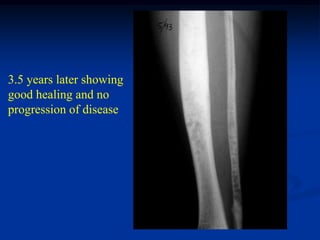

3.5 years later showing

good healing and no

progression of disease

Lateral view at same time